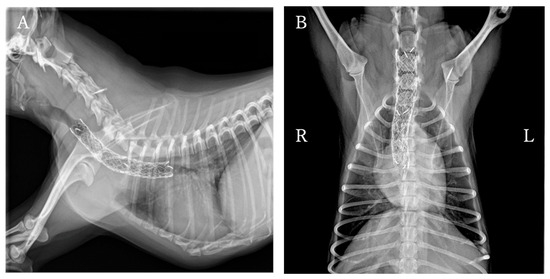

Tracheal stent fracture is a major complication of endoluminal tracheal stent (ELS) for canine tracheal collapse, and optimal management strategies remain unclear. A 4-year-old Yorkshire Terrier presented with respiratory distress caused by complete ELS fracture. Imaging and bronchoscopy revealed intraluminal protrusion of fractured stent segments, ventral tracheal cartilage invagination, and marked luminal deformation. A polypropylene linear prosthesis (PLLP) was selected as an external tracheal support. Its continuous band-like structure allowed broad and uniform reinforcement of the tracheal wall and redistribution of mechanical stress. PLLP placement successfully restored a near-normal tracheal contour and stabilized the fractured stent without introducing additional intraluminal material. Postoperative bronchoscopy confirmed improved tracheal patency, and no further deformation or stent damage was observed despite several months of altered airway dynamics associated with laryngeal paralysis. This case suggests that PLLP may represent a valid surgical option for managing tracheal stent fracture in dogs. Full article